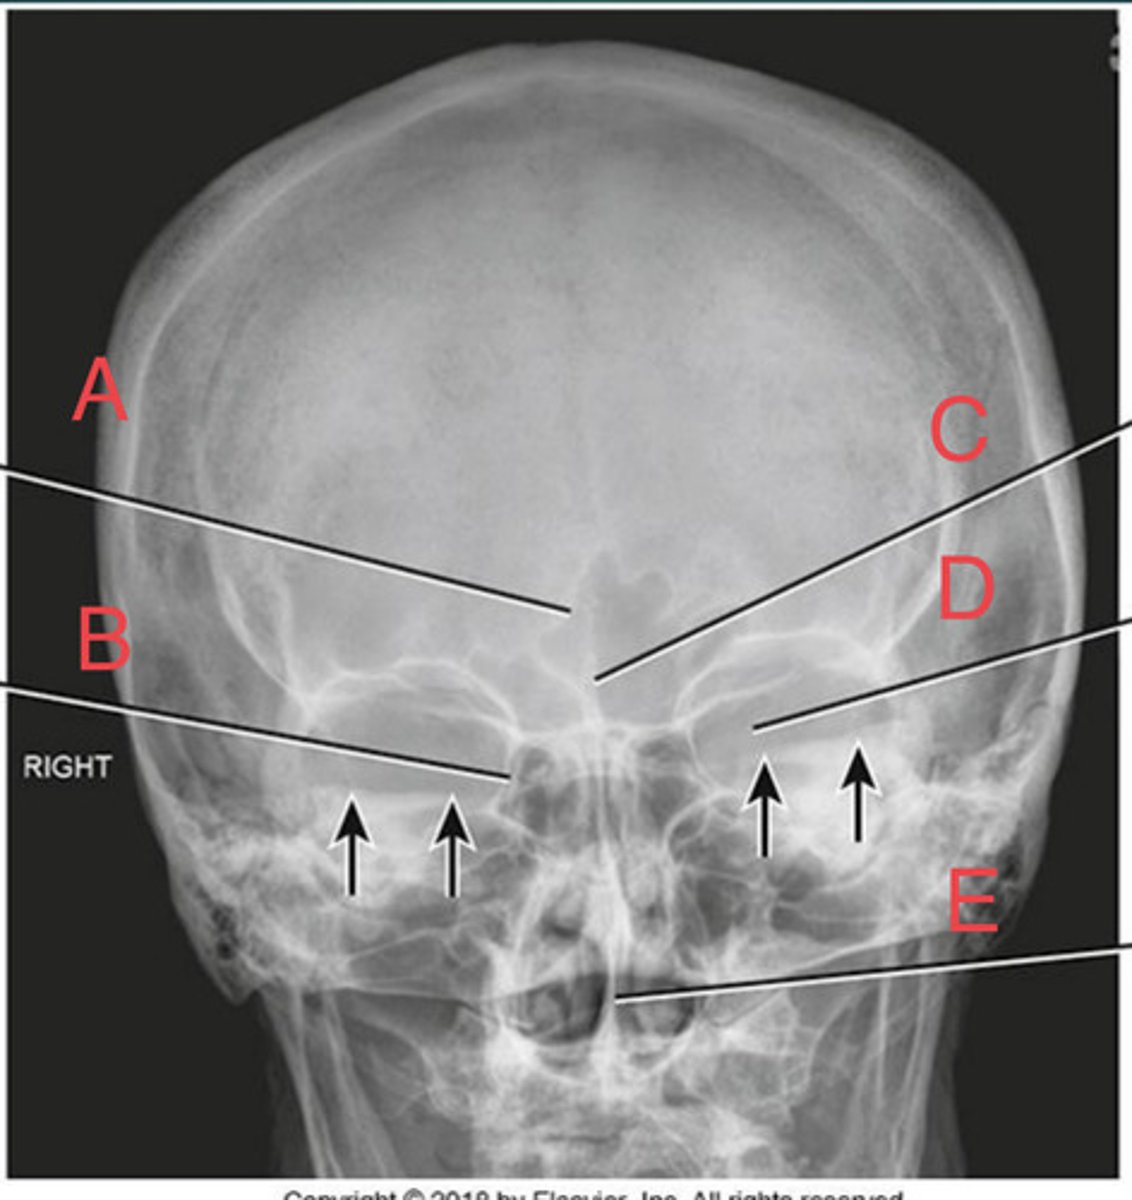

PA Caldwell Sinuses

What position?

frontal sinus of the frontal bone

A.

R. ethmoid sinus of the ethmoid bone

B.

crista galli of ethmoid bone

C.

L superior orbital fissure of the sphenoid

D.